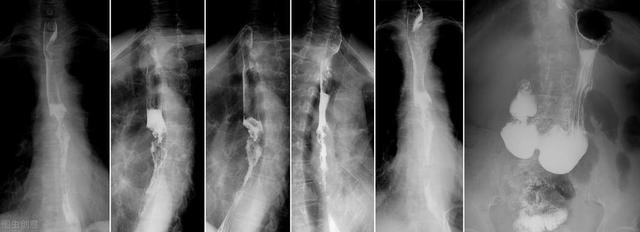

3、食管吞钡X线检查。对于比较典型的反流性食管炎,食管吞钡X线一般能诊断。当然,对于部分反流性食管炎,吞钡检查可能无法明确诊断,但它可以排除食管癌等其他食管疾病,同时相对于胃镜检查,它更加简单易行,对病人造成的痛苦也小,这是它的优势,所以对于部分患者可以作为筛查使用。